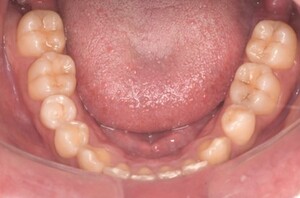

症例5

before

症例

after

歯周病検査(治療前)

歯周病検査(治療後)

レントゲン写真

基本情報

年齢・性別 32歳・男性

主訴 主訴:歯ぐきから出血する

治療部位:全顎

治療内容 「全顎」

歯周基本治療(歯周精密検査、スケーリング、OHI、SRP)

治療期間 約3ヶ月

治療費 歯周基本検査:約600円(保険診療3割負担)

スケーリング、OHI:約2,000円(保険診療3割負担)×2回

SRP、OHI:約1,500円(保険診療3割負担)×4回

歯周精密検査:約1,200円(保険診療3割負担)×2回

合計金額13,000円

(2025年2月現在)

リスク・副作用 歯石を取った後に、歯がしみることがあります。

治療方針 ①検査

レントゲン、口腔内写真を撮影して、歯や歯周組織の状態を確認します。

また、歯周病の検査で歯周ポケットの深さや出血の有無を確認します。

②スケーリング、OHI(口腔衛生指導)

スケーリングをして歯の表面の歯石を除去します。

また、正しい歯磨きの仕方や、フロスの通し方を一緒に確認します。

③歯周精密検査

前回歯石除去と歯磨き指導を行なった結果、歯ぐきの状態がどれぐらい改善したか検査します。

④SRP

歯ぐきの内側についてる歯石を除去します。

⑤歯周精密検査

SRP後、歯周病が改善されたか、検査します。

歯周ポケットが4ミリ以上の部位は、再度SRPを行います。

今回は歯周病の状態が安定したため、3ヶ月おきの定期検診で歯周病の再発や進行を防ぎます。

特記事項 歯周精密検査について:

・歯周ポケットが4ミリ以上ある場合は歯周病で、3ミリ以下は健康な歯ぐきです。

・出血の有無で炎症があるか確認します。

・磨き残しがある部分を確認して記録します。

担当者所見 初診時は、写真を見て分かるように、歯ぐきが赤く腫れていました。

また、歯周病の検査では、全体的に歯と歯の間の部分の歯周ポケットが4ミリあり、全体の約81%から出血が認められました。

出血量も多く、歯ぐきに触れた瞬間に出血しました。

レントゲンで骨のレベルがしっかりとあることが確認できました。

そのため、ご自身で正しい歯磨きを継続することで改善すると考えました。

歯周基本治療を経て、再度検査した結果、歯周ポケットはほぼ3ミリ以下に改善しました。左下7番の残存した歯周ポケットは、隣の親知らずを抜いたため経過観察します。

出血率は約4%まで改善し、出血量も点状で少なくなりました。

今後は右上2番、右下3番の歯ぐきの発赤の改善と、出血率0%を目指して、定期検診でメンテナンスしていきます。